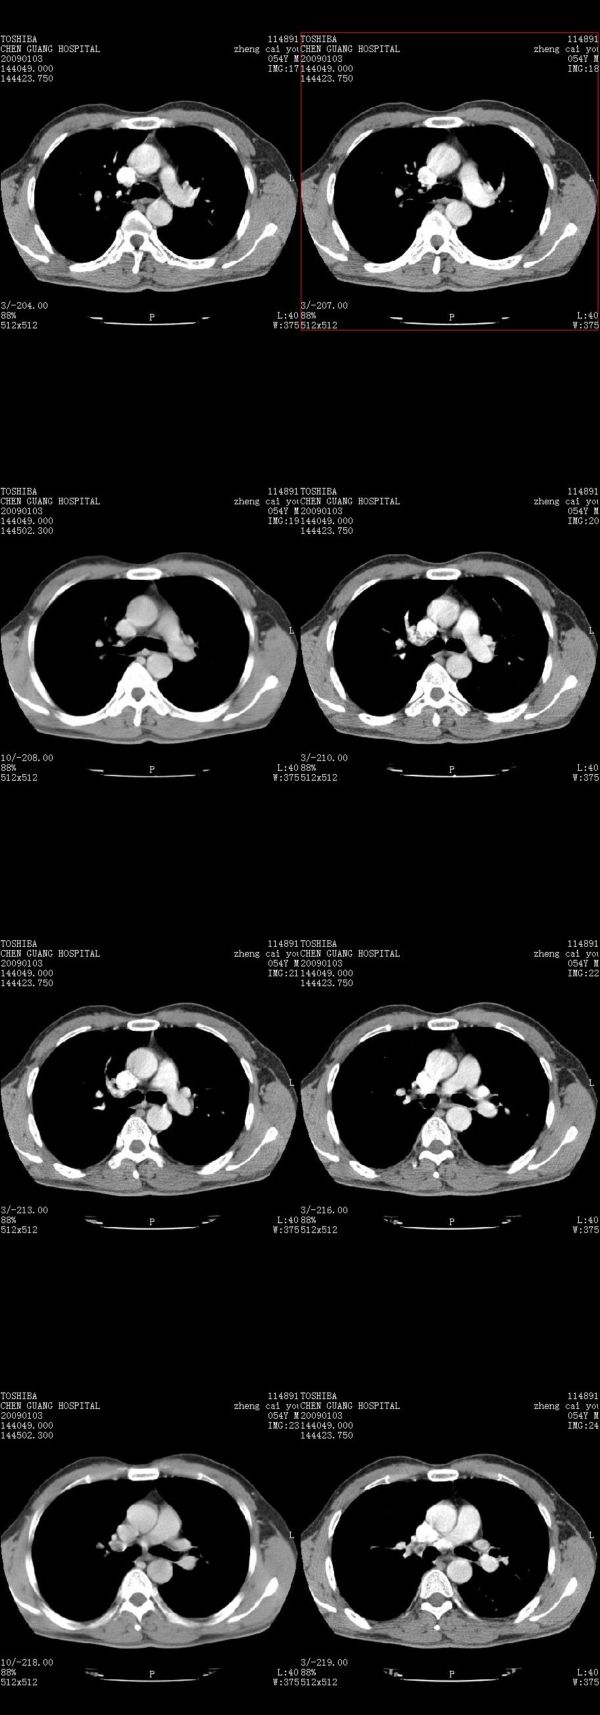

男,54岁,右侧胸部疼痛,平时吸烟,有抽烟后咳嗽咯痰史。昨天没把xiphoid软件吃懂,所以没把纵隔窗图像处理出来!请各位老师帮忙看一下右肺门有没有问题?谢谢!!!!!!!!!!

右肺上叶后段近气管旁仍可见一结节灶,不除外为肿大的淋巴结影。

我同学讲红线部分强化不好,感觉不是很舒服,这是什么道理?

我同学讲红线部分强化不好,感觉不是很舒服,应该 是软组织间隙,不是一个孤立的病灶。

气管前腔静脉后似见增大淋巴结影,肺门区未见明显肿块影。肺窗示右肺中叶外侧段透亮度增高,可过一段时间再查一下对比一下,毕竟是自己的至亲,又有条件,辐射就顾不得了。

也觉得还好吧,只是右下肺动脉显粗了点,纵膈有钙化淋巴结,再有肺窗就更好了

各位老师:奇静脉增宽,肺上未见明显实变,这还需注意观察些什么?????

右侧肺门影增大,不除外增大淋巴结可能

上腔静脉后淋巴结影,不知道最后结果怎么样?